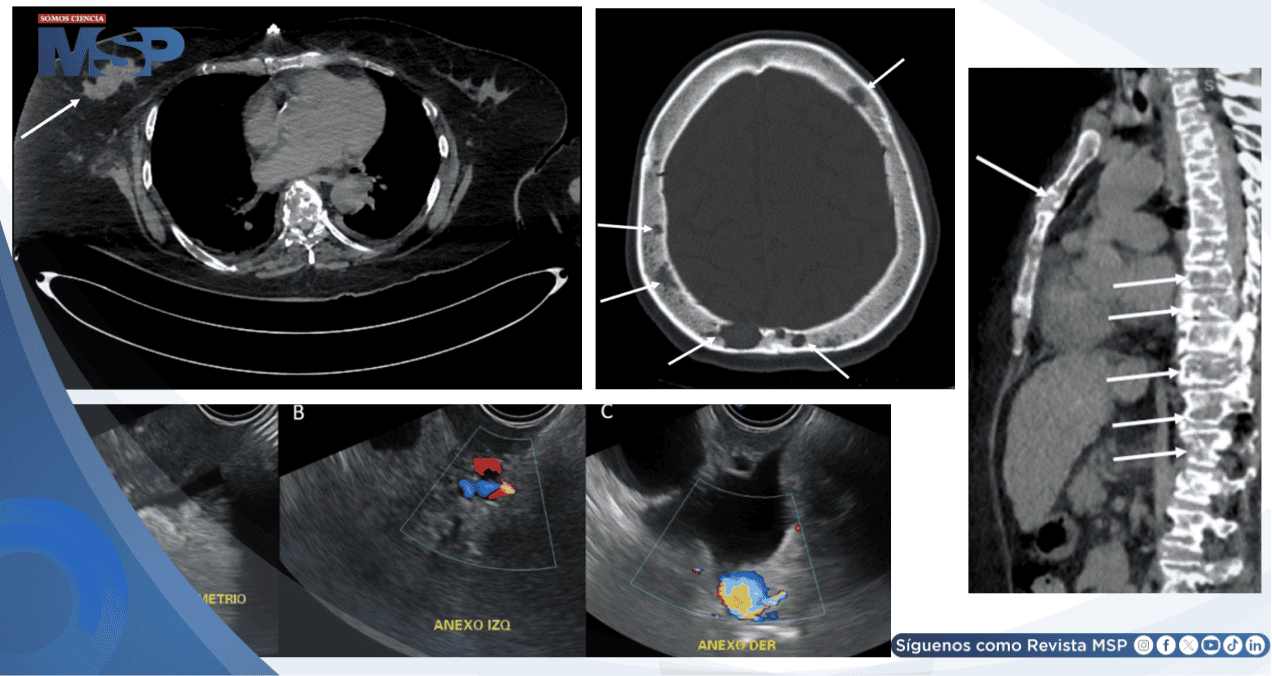

La tomografía computarizada de tórax, abdomen y pelvis reveló múltiples lesiones óseas osteolíticas en sacabocados y ganglios aumentados de tamaño en el retroperitoneio, hallazgos que inicialmente sugerían mieloma múltiple.

Sin embargo, el mismo estudio identificó una lesión sólida en la mama derecha, la cual fue caracterizada posteriormente mediante ecografía mamaria. Este examen mostró una masa irregular de 5 por 3 centímetros, con características altamente sospechosas de malignidad, clasificada como BI-RADS 5, acompañada de ganglios axilares infiltrados.

Los marcadores tumorales se encontraban notablemente elevados, incluyendo CA 15-3 y CEA. Finalmente, se realizó una biopsia de la mama derecha, cuyo resultado confirmó la presencia de un carcinoma ductal invasivo de mama con receptor HER2 positivo. Este estudio estableció el diagnóstico definitivo de cáncer de mama metastásico como causa de la hipercalcemia maligna y, consecuentemente, de la pancreatitis aguda secundaria.